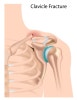

쇄골 골절(Clavicle fracture) : 넘어지면서 어깨를 땅에 부딪히면서 쇄골이 부러졌어요

대개 어깨로 넘어지거나, 직접 쇄골 부위를 부딪히는 것과 같은 견관절 부위의 타격에 의해 발생합니다.

내측 골편은 SCM에 의해 근위로 들리게 되고, 외측 골편은 상지의 무게로 아래쪽으로 내려가는 것이 전형적인 변형입니다.